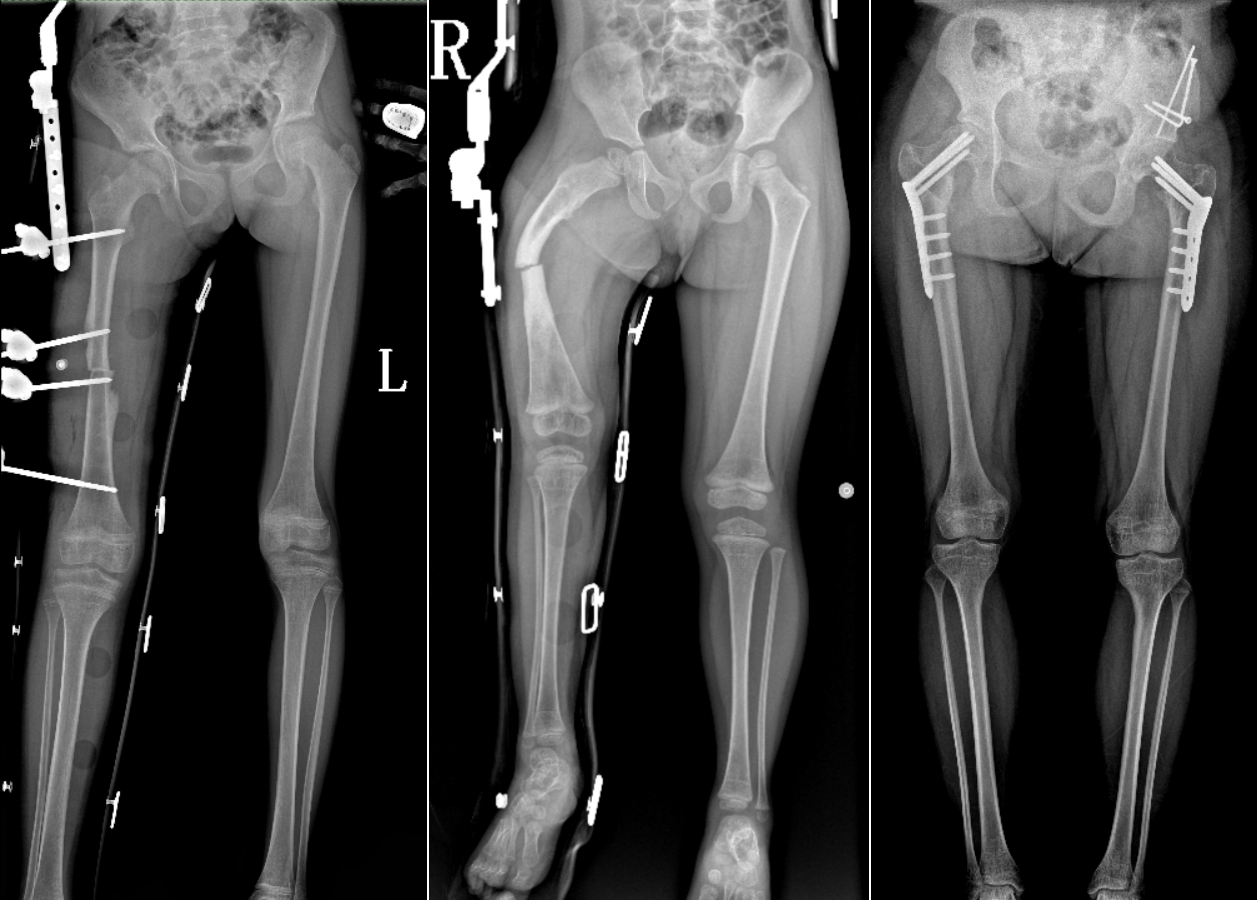

DR是臨床骨科的重要檢查手段之一。在骨科檢查中,脊柱矯形、長(zhǎng)骨骨折、腰椎退行性病變等,需要采集脊柱、下肢全景圖像,輔助醫(yī)生臨床診斷,從而制定科學(xué)的治療方案,普愛(ài)醫(yī)療的大視野平板動(dòng)態(tài)DR就像是一座橋梁,連接起現(xiàn)代醫(yī)療技術(shù)與當(dāng)?shù)厝嗣竦尼t(yī)療需求。

普愛(ài)醫(yī)療自主研發(fā)的大視野平板動(dòng)態(tài),采用17"*34"的有效視野,一次曝光即可得到全脊柱或全下肢影像。相較于多張攝影再軟件拼接的DR設(shè)備,PLX8600解決了拼接圖像存在密度不均勻,拼接處圖像配準(zhǔn)和放大效應(yīng)等問(wèn)題,給臨床帶來(lái)了真正的大視野影像解決方案。